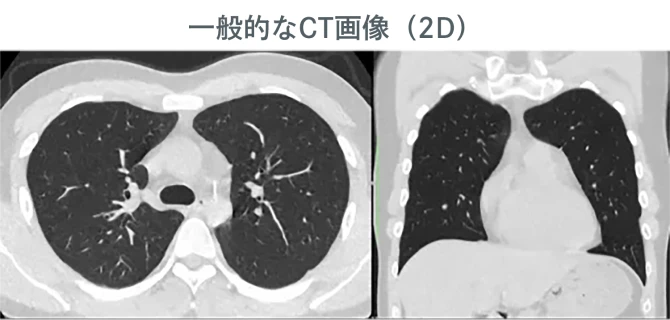

肺+心臓CTとは、胸部全体を撮影し、肺や心臓の状態をすみずみまで詳しく調べる検査です。一般的な健康診断のレントゲンでは見つけにくい病気のサインや、ごく小さな異常を発見することに優れています。

リアル3D画像

当院の画像は高画質なだけでなく、リアル3D画像も作成し、お渡しします。

病変の大きさ、形状、周囲組織との位置関係などを立体的に評価できるため、診断の正確性が向上します。また、異変が視覚的にわかりやすいため、受診者様も理解が容易になります。